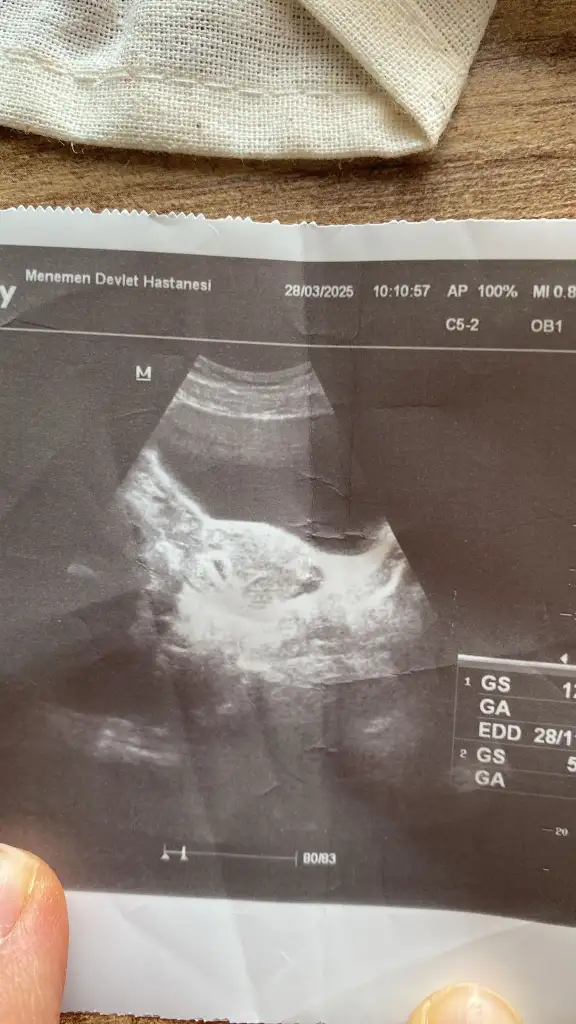

İnanın ultrasyon boş hiç birşey yok şaşırdım bende bilen birine attım keseyi zor gördüSenin ikiz olabilir birisi arkadan geliyor ama önemli değil önemli olan sağlıcakla büyümesi sonradan kardeşini yakalar inşallahultrason resmini tam atsaydın belki

çözerdik buradaki deneyimli bayanlarla beraber hayırlısı olsun çok takma kafana sağlıcakla gelsinler inşallah

İnanın ultrasyon boş hiç birşey yok şaşırdım bende bilen birine attım keseyi zor gördüdevlet olunca önemsemiyorlar babacım bizleri

Şöyle varmı kiSenin ikiz olabilir birisi arkadan geliyor ama önemli değil önemli olan sağlıcakla büyümesi sonradan kardeşini yakalar inşallahultrason resmini tam atsaydın belki